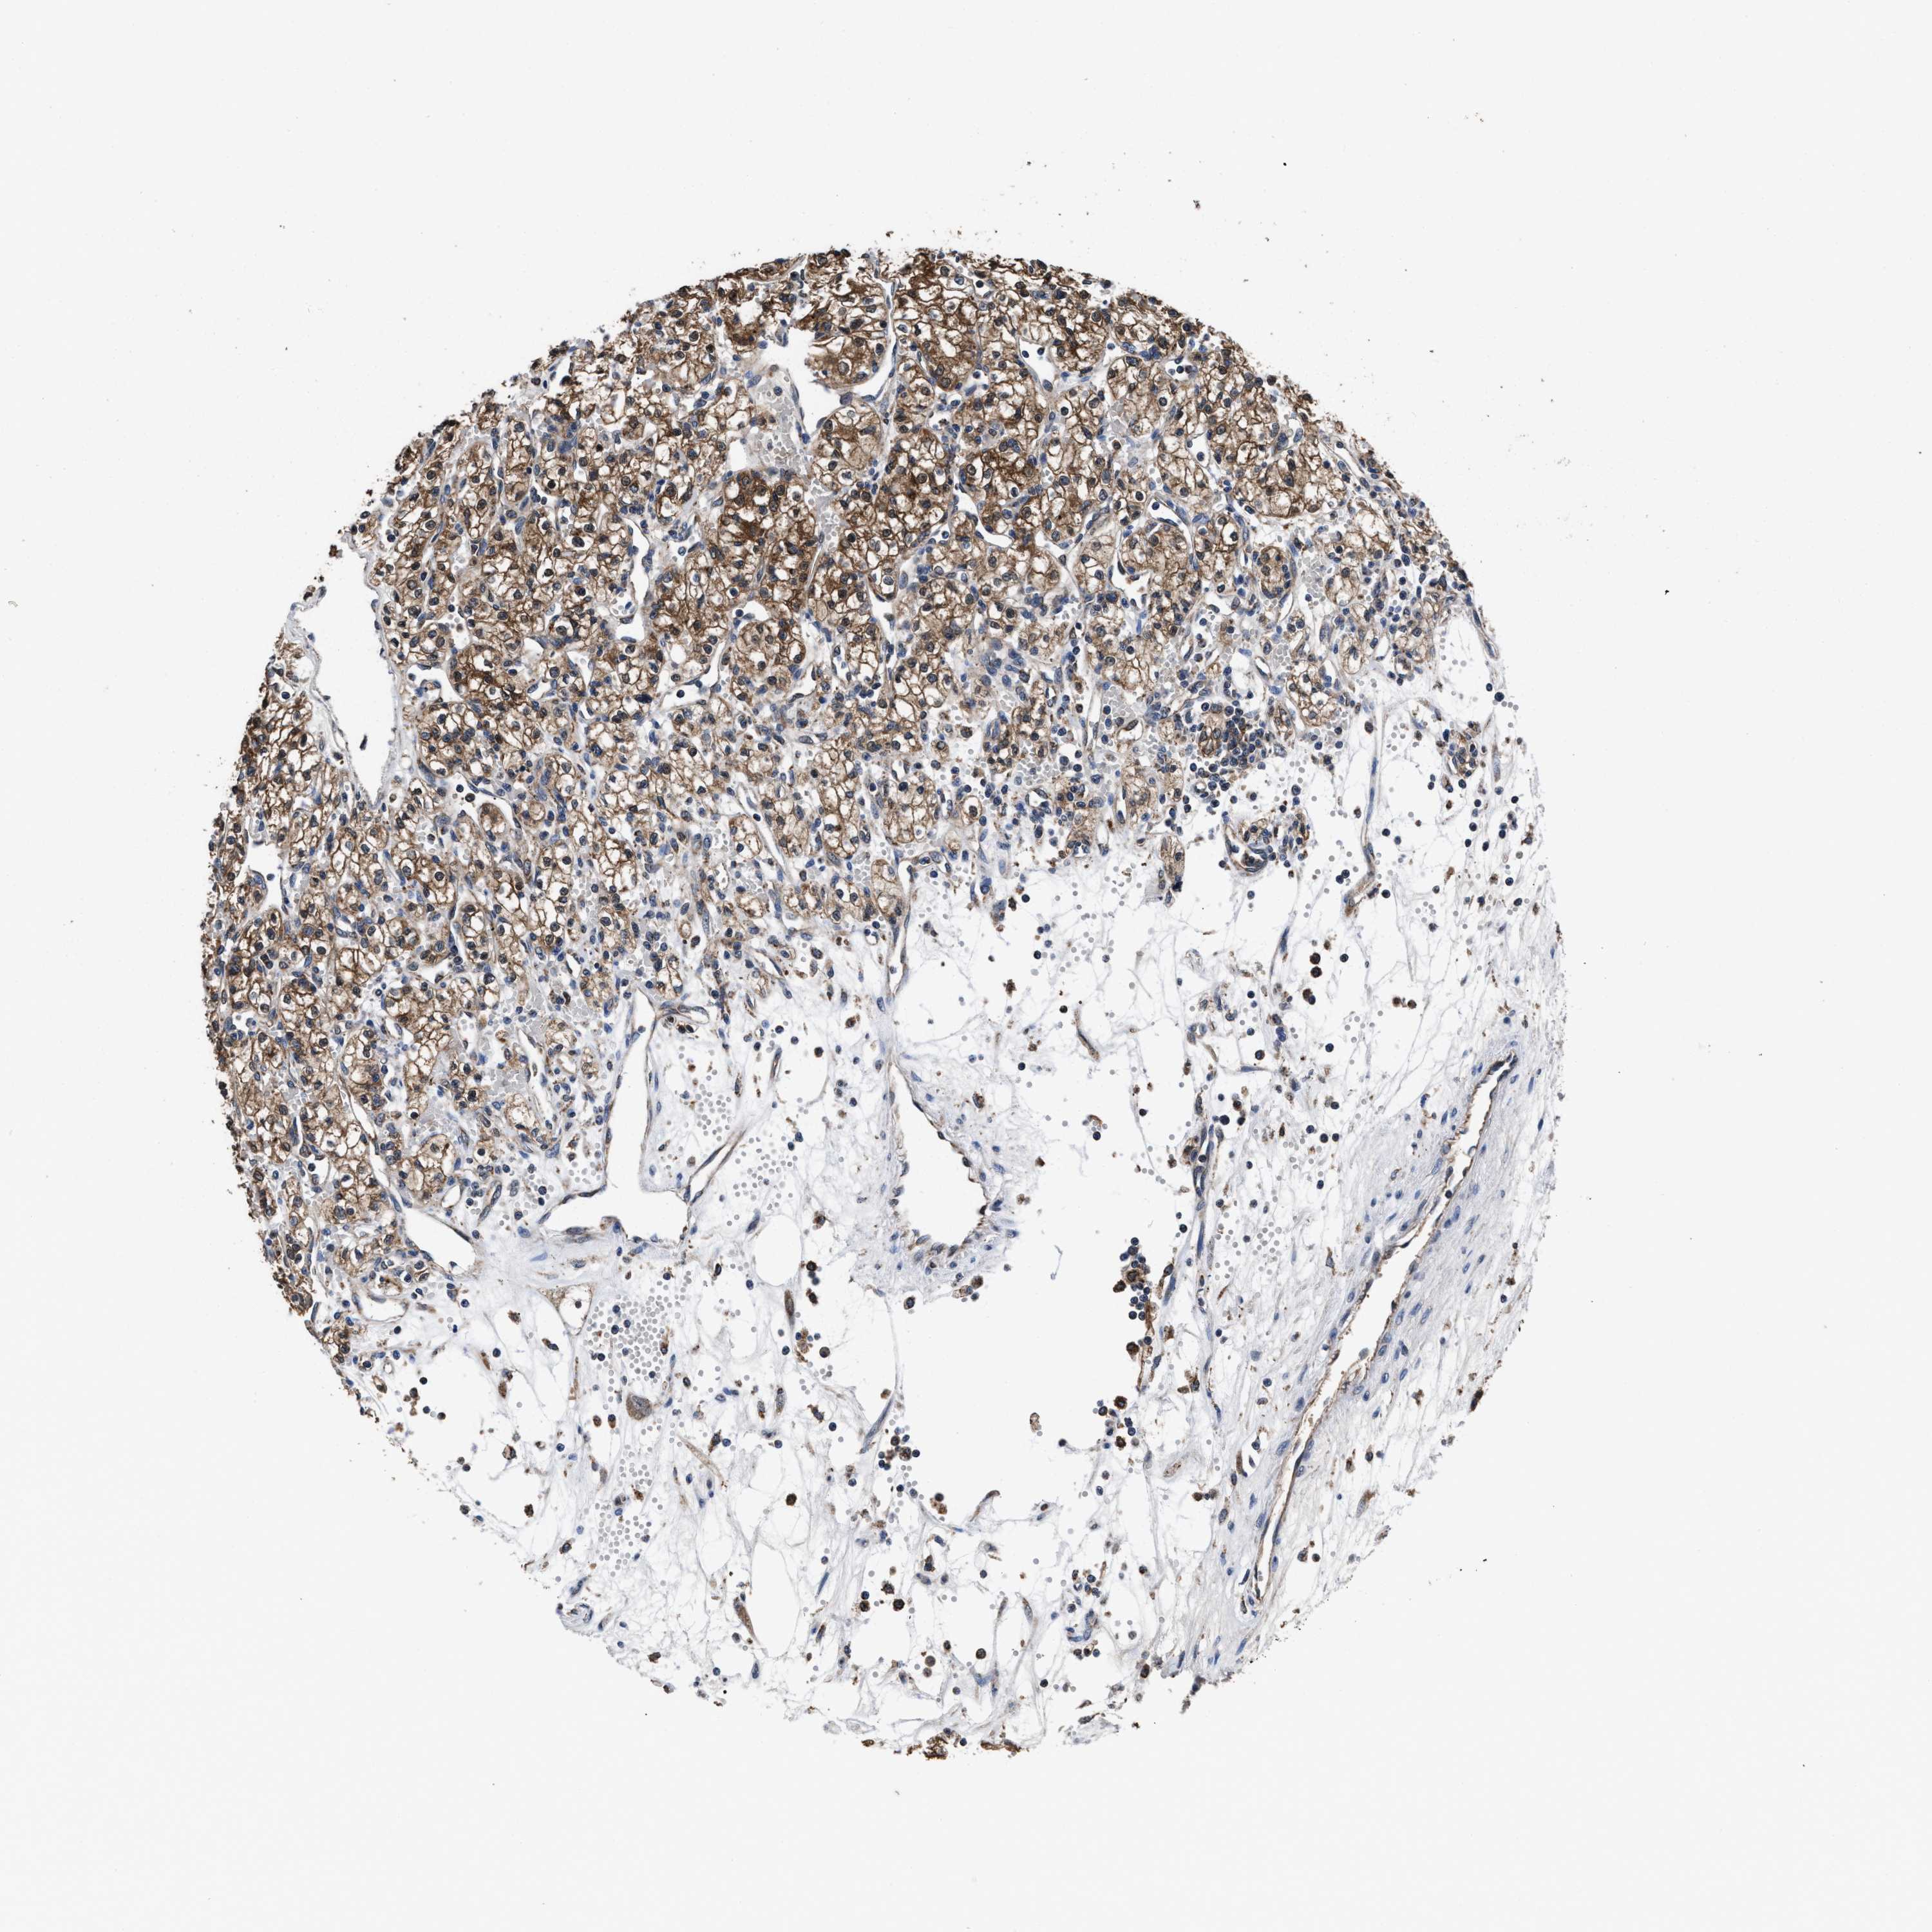

KIDNEY RENAL CLEAR CELL CARCINOMA (VALIDATION) - Interactive survival scatter ploti

The Survival Scatter plot shows the clinical status (i.e. dead or alive) for all individuals in the patient cohort, based on the same data that underlies the corresponding Kaplan-Meier plots. Patients that are alive at last time for follow-up are shown in blue and patients who have died during the study are shown in red.

The x-axis shows the expression levels (FPKM) of the investigated gene in the tumor tissue at the time of diagnosis. The y-axis shows the follow-up time after diagnosis (years). Both axes are complimented with kernel density curves demonstrating the data density over the axes. The top density plot shows the expression levels (FPKM) distribution among dead (red) and alive patients (blue). The right density plot shows the data density of the survived years of dead patients with high and low expression levels respectively, stratified using the cutoff indicated by the vertical dashed line through the Survival Scatter plot. This cutoff is automatically defined based on the FPKM cutoff that minimizes the p-score. The cutoff can be changed by dragging the vertical line or by entering a cutoff value in the square labeled "Current cut-off".

Under the Survival Scatter plot the p-score landscape (black curve; left axis) is shown together with dead median separation (red curve; right axis). Dead median separation is the difference in median mRNA expression between patients who have died with high and low expression, respectively. It is calculated as follows: median FPKM expression of dead patients with high expression - median FPKM expression of dead patients with low expression. This is intended to aid the user in visually exploring custom cutoffs and the associated p-scores and dead median separation.

Individual patient data is displayed and can be filtered by clicking on one or more of the category buttons on the top of the page. Categories describing expression level and patient information include: high, low, alive, dead, female, male and tumor stages. The scale of the x-axis can be toggled between linear and log-scale by clicking on the "x log" button. Mouse-over function shows TCGA ID, patient information and mRNA expression (FPKM) for each patient.

& Survival analysisi

Kaplan-Meier plots summarize results from analysis of correlation between mRNA expression level and patient survival. Patients were divided based on level of expression into one of the two groups "low" (under cut off) or "high" (over cut off). X-axis shows time for survival (years) and y-axis shows the probability of survival, where 1.0 corresponds to 100 percent.

ACLY is not prognostic in Kidney Renal Clear Cell Carcinoma (validation)

Best expression cut offi

Based on the FPKM value of each gene, patients were classified into two groups and association between prognosis (survival) and gene expression (FPKM) was examined. The best expression cut-off refers the FPKM value that yields maximal difference with regard to survival between the two groups at the lowest log-rank P-value. Best expression cut-off was selected based on survival analysis .

When clicking on this number, the vertical dashed line indicating cut-off, the interactive survival plot, and the Kaplan-Meier curve will be adjusted to show results based on the best expression cut-off.

: 169.05

Median expressioni

Median expression refers to the median FPKM value calculated based on the gene expression (FPKM) data from all patients in this dataset. When clicking on this number, the vertical dashed line indicating cut-off, the interactive survival plot, and the Kaplan-Meier curve will be adjusted to show results based on the median expression.

: N/A

TCGA RNA samplesi

RNA-seq data is reported as average FPKM (number Fragments Per Kilobase of exon per Million reads), generated by the The Cancer Genome Atlas (TCGA) .

Normal distribution across the dataset is visualized with box plots, shown as median and 25th and 75th percentiles. Points are displayed as outliers if they are above or below 1.5 times the interquartile range. FPKM values of the individual samples are presented next to the box plot.

Average pTPM 211.9

Number of samples 100